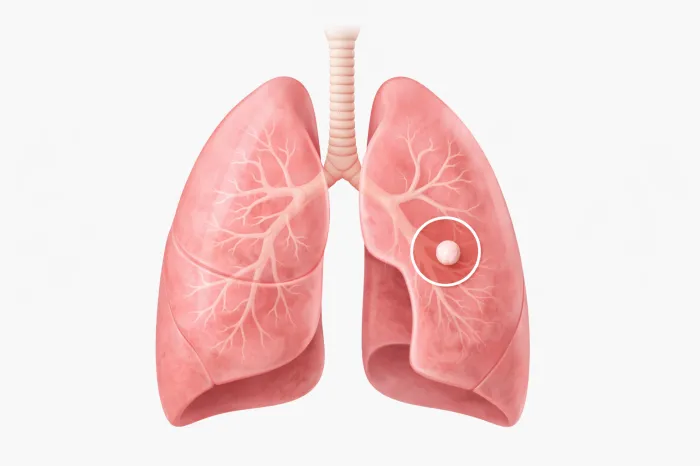

➜ 폐결절이 모두 위험한 것은 아닙니다

폐결절 은 양성 결절인 경우가 훨씬 많습니다. 과거 감염, 염증 반응, 흉터 등으로 인해 남은 흔적인 경우가 많습니다. 특히 크기가 작고, 가장자리가 매끄러우며, 오랜 기간 변화가 없다면 양성일 가능성이 높습니다.

반면 크기가 점점 커지거나, 모양이 불규칙한 경우에는 보다 면밀한 관찰이 필요합니다. 이때는 의사의 판단에 따라 추가 검사나 추적 촬영이 진행됩니다.